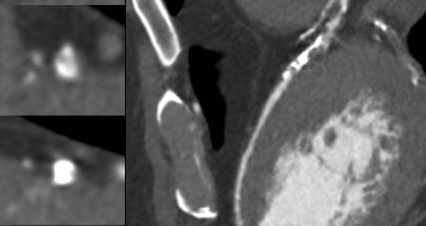

Coronary angiography showed multivessel coronary artery disease, including a severe, long stenosis in a large posterolateral branch of the right coronary artery (RCA), diffuse severe disease in the left circumflex artery (LCX), and a severely calcified chronic total occlusion (CTO) of the mid left anterior descending artery (LAD).

Antegrade wire escalation was attempted using a Corsair ProXS 135 cm (Asahi Intecc) and multiple guidewires, including the Fielder XT, Gaia Next 2, and Gaia Next 3 (Asahi Intecc). However, none of the guidewires were able to successfully cross the occlusion. Hydrodynamic recanalization (HDR) was then attempted. Followig a 0.5 cc tip injection of contrast no progress was achieved. A second HDR injection was performed, after which a Gaia Next 2 guidewire successfully crossed the CTO to the distal LAD. However, the Corsair Pro XS microcatheter failed to cross the distal cap and became fatigued during manipulation. An anchoring technique with a 1.5 ¡¿ 15 mm SC balloon in the septal branch was performed in an attempt to support crossing of the Caravel microcatheter (Asahi Intecc), but the distal cap remained uncrossoable. Caravel microcatheter was left within the CTO body, and a floppy Rotawire Drive guidewire (Boston Scientific) was advanced to the distal LAD. Rotational atherectomy was then carried out with a 1.5 mm burr using the Rotapro system (Boston Scientific) at 180,000–200,000 rpm for a total of 8 minutes. IVUS imaging using Opticross (Boston) confirmed true lumen crossing, presence of circumferential calcification, reverberation as well as superficial plaque fractures. Sequential predilatation with a Wolverine cutting ballon was performed and then definite stenting was accomplished with a 3.5x48 mm and 4.0x38 mm Synergy XD extending from mid LAD into left main